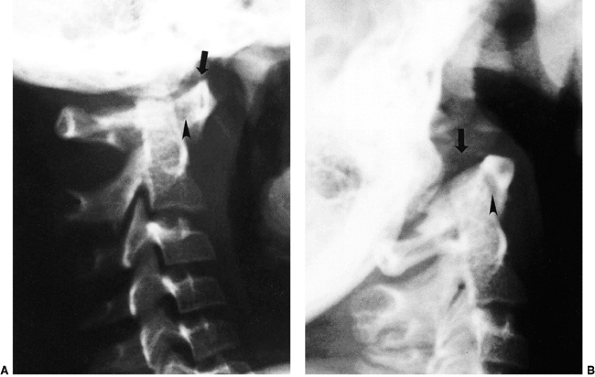

Figure 22.3

Lateral view of the atlantoaxial joint. The atlantodens interval (ADI) is the distance between the anterior aspect of the dens and the posterior aspect of the anterior portion of the ring of the atlas. The space available for the cord (SAC) is the distance between the posterior aspect of the dens and the anterior aspect of the posterior portion of the ring of the atlas. In children, an ADI of 5 mm or larger is abnormal. In teenagers and adults, a SAC of 13 mm or smaller can be associated with canal compromise. In younger children, spinal cord impingement is imminent if the SAC is equal to or less than the transverse diameter of the odontoid. A: The relations in extension. B: The relations in flexion. |

extension radiographic views, with the movements performed voluntarily

atlas (Fig. 22.3). An ADI of more than 5 mm on flexion and extension lateral radiographs indicates instability (29,30).

Figure 22.4 Lateral flexion (A and extension) B

radiographs of an 11-year-old boy with Down syndrome. The child presented with loss of hand control when flexing his neck. Using the method of Tredwell et al. (37), the atlantooccipital distance is measured as the distance between the anterior margin of the condyles at the base of the skull and the sharp contour of the anterior aspect of the concave joint of the atlas. More than 4 mm of posterior translation is abnormal. The atlantooccipital distance (arrows) measures 10 mm in extension and 1 mm in flexion. The atlantodens interval is 1 mm in extension and 6 mm in flexion, for a total of 5 mm of motion (arrowheads). The space available for the cord is 17 mm in flexion and 20 mm in extension. Both occipitoatlantal instability (more than 4 mm posterior translation) and atlantodens hypermobility (5 mm atlantodens interval in flexion) are present. |